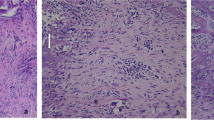

Figure 1 shows the optical microscopic views of the tooth extraction sockets on every experimental day in all the groups. Three days after extraction, the sockets in group 1 were filled mainly with red blood cells (RBCs), inflammatory cells, and fibroblasts from the remnants of the periodontal ligaments (PDL). In group 2, there was less infiltration of inflammatory cells than observed in the non-irradiated group, and newly formed collagen fibers, osteoclasts, and more fibroblasts were observed. In group 3, many inflammatory cells and RBCs were densely infiltrated near the top of the socket. Fewer fibroblasts and collagen fibers than in the other groups were observed. In group 4, there were fewer inflammatory cells and RBCs and more infiltrated fibroblasts than in group 3.

Optical microscopic views of the tooth extraction sockets (H&E stain). The differences in healing were dependent on whether the sockets had received laser irradiation. LLLT promoted not only early healing, such as the reduction of inflammatory cells and the proliferation of fibroblasts but also the emergence of osteoblasts and bone formation under both normal and diabetic conditions. At day 14, the original magnification 40× was used to observe the entire socket. The amount of new bone and osteoid tissue was higher in group 2 than in group 1 and higher in group 4 than in group 3

Five days after extraction, the RBCs had almost disappeared in all groups and newly formed vessels, connective tissue, and fibroblasts were observed. In group 2, the collagen fibers were denser near the residual PDL, and osteoid tissue and lining osteoblasts were observed from the base area of the socket. In groups 1 and 4, concentrated fibroblasts, thick collagen fibers around them, osteoblasts, and some osteoid-like matrix were observed near the old alveolar bone.

At 7 days, new bone, osteoid and lining osteoblasts around them were observed in all groups, but there were some differences in the amount of new bone and osteoid tissue. There were more cells and connective tissue than at 5 days.

At 14 days after extraction, new bone, lining osteoblasts, osteocytes, osteoid, thick collagen fibers, and fibroblasts were observed in all groups. In group 2, the sockets were almost completely filled with new bone and there was more new bone than in group 1. In group 3, bone formation was poorer than any of the other groups. Only one-third of the sockets were filled with new bone; the remainder were filled with connective tissue. In group 4, new bone filled approximately one-half of the socket. Bone formation in group 4 was more prominent than in group 3.

The results of this study also showed a biostimulatory effect of LLLT on the alveolar bone of both normal and diabetic rats. In group 2, osteoblasts and osteoid tissue were observed at day 5, which was earlier than in the control group, and new bone reached the top of the extraction socket at day 14. In group 3, healing was much slower than in group 1. At day 3, considerable infiltration of inflammatory cells and blood clots in the superficial part of the sockets were observed in group 3. The amount of new bone and osteoid tissue in group 3 was the lowest of all the groups at days 7 and 14. In group 4, much less infiltration of inflammatory cells and blood clots were observed than in group 3 at day 3, and more new bone formed at days 7 and 14 than in group 3, even though only half of the extraction socket was filled with new bone at day 14. The differences in healing were dependent on whether the sockets had received laser irradiation. LLLT promoted not only early healing, such as the reduction of inflammatory cells and the proliferation of fibroblasts but also the emergence of osteoblasts and bone formation under both normal and diabetic conditions.